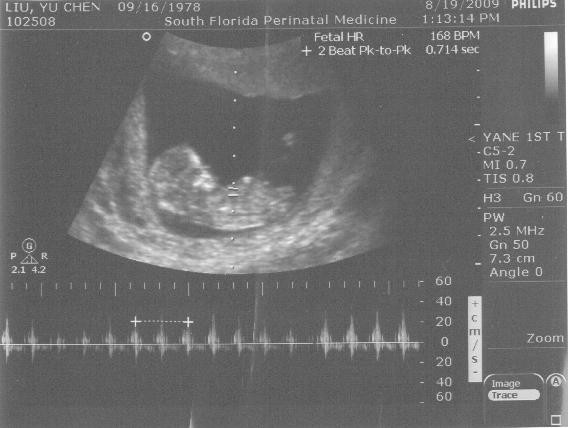

先做超音波檢驗,當我把肚子露出來時,覺得冷氣怎麼好像吹到小肚肚上了,還在擔心著待會抹上超音波液的時候會涼咻咻。不過還好這個液體溫溫的(前兩次照超音波好像也是溫暖的,我本來一直以為是冰涼的,不知道是不昰有加溫過,真是感心啊~),而且想不到當儀器一放在肚子上時,在螢幕上立刻顯現一個小人形狀,天啊~這ㄧ個月的變化也太大了吧?~上個月看還是小點點一顆,現在竟然形態都出現了,頭、手、腳都已經看得到,且因為身體呈半透明,還可以看到小心臟噗通噗通跳著哩!今天也聽了心跳聲,頻率還是很快,而且聲音好奇怪唷~是個我完全無法再模仿的聲音,小貝比真是太神奇的東西了~

今日的小黑點生長情形:

很神奇吧~已經是個人的形狀了耶~

有看到小手手與手指頭嗎?真是可愛~鍵哥說看到鼻子了,想不到還這麼小鼻子就很清楚,以後應該會鼻子挺挺像鍵哥一樣吧?~哈哈~

下面聲音頻率的東西,就是心跳啦~